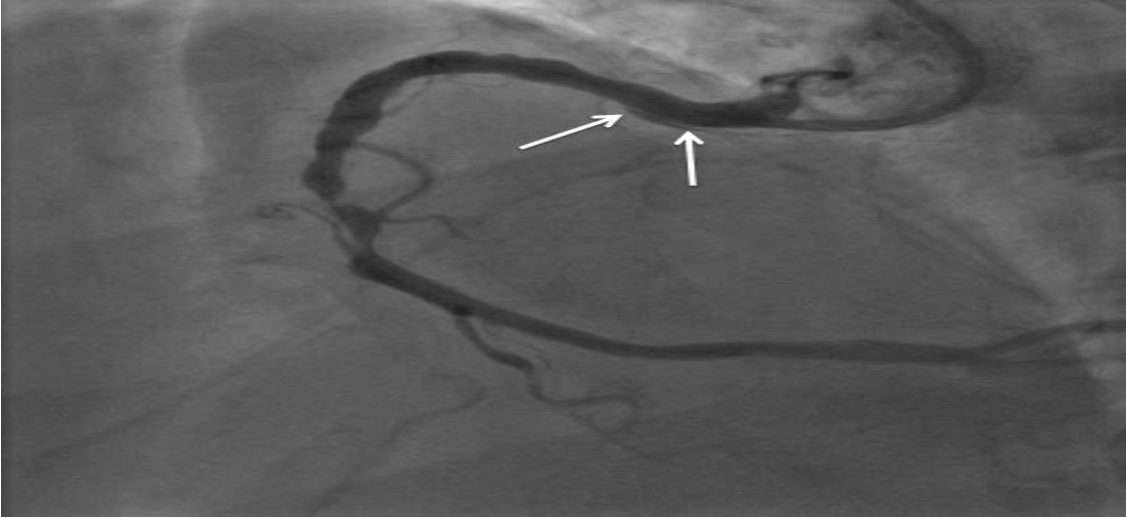

After two hours, the patient developed right hemiplegia and aphasia. A cerebral CT scan revealed a left ischaemic stroke in the anterior junctional territory. CT angiography of the supra-aortic arteries showed a dissection of the left internal carotid artery. However, CT angiography of the aorta revealed no abnormalities (Figure 2). Coronary angiography performed after 48 hours showed dissection of the anterior inter-ventricular artery (Figure 3).

no further interventions, as distal coronary flow was reasonable. After a multidisciplinary staff meeting, a consensus was reached in favor of conservative management. A statin (atorvastatin at 80 mg/day) was started and anti-coagulant therapy was discontinued. The course was marked by persistent ST-segment elevation despite an increase in Troponin I levels (2000 ng/l).